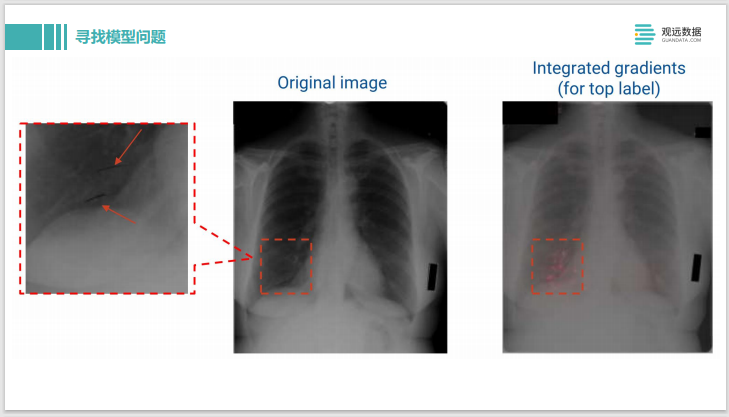

这是利用IG – Integrated Gradients,做 X光片的疾病诊断。可以看到原始输入的图片是左边。输出的 label是这个人有疾病,我们用了 IG去做解释后,可以看到右边这边有一些粉红色的高亮,这表示在这些像素点上的模型认为样本被分类为有问题,是贡献度最大的像素点。

我们可以再把像素点放大,看看模型到底是做了什么样的判断。结果发现这个其实是上面有两条用黑色记号笔画的线,应该是医生在诊断过程中看了X光片,确诊出来有问题,就在这边画了两条马克笔的线,那模型学到的是医生的标记,并不是学到了病理组织的 pattern,所以模型的判断其实是有问题的。这样就可以很方便的通过模型解释的方法去找到模型中的一些弱点。